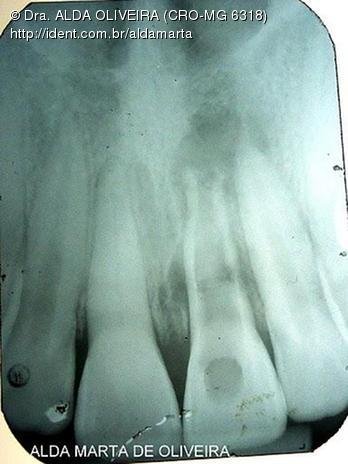

Reabsorção Pós Traumatismo Dente 21

Caso clínico, 20 de Nov de 2010

Paciente de 11 anos.

Queixa principal: dor no dente 21.

Pela anamnese relatou ter sofrido traumatismo há 2 anos e início de tratamento endodôntico, que foi abandonado...

Por mim, infelizmente o dente está condenado, mas pedi autorização ao pai para radiografar a garota (pois esta radiografia que trouxe não estava bem nítida...) e só assim eu daria minha decisão final, se valeria à pena tentar algum tratamento ou não...

Porém o pai ficou indeciso... daí só fotografei rapidamente o dente da garota e a radiografia que eles trouxeram.

"Por Fora Bela Viola... por Dentro, Pão Bolorento!"